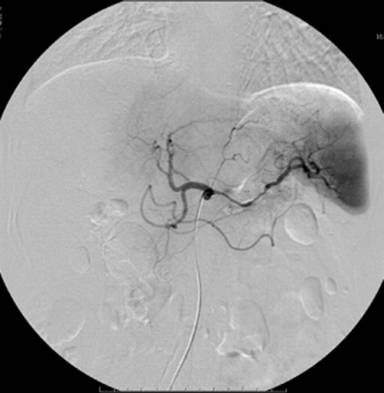

An endoscopy of the upper gastrointestinal tract showed a submucosal tumor, about 4 cm in diameter, located in the posterior wall of the gastric body (Figure 1). The results of the bioptic specimen could not be diagnosed pathologically. MRCP showed neither dilation nor irregularity of the main pancreatic duct (Figure 2). A CT scan demonstrated an ill-defined, irregular solid mass, 6x6x7 cm in size, situated between the retroperitoneum, the pancreas and the lesser curvature of the stomach (Figure 3). The tumor seemed to originate from the retroperitoneum with invasion of the stomach and pancreas. The left gastric artery and the splenic artery were compressed by the tumor which was located adjacent to the celiac axis. Celiac angiography indicated encasement of the splenic artery (Figure 4). Superior mesenteric artery angiography and portography were unremarkable. The tumor was essentially hypovascular. Although a definitive diagnosis was uncertain on the basis of the imaging findings described above, primary neoplasms including malignant mesenchymal tumors were taken into consideration preoperatively.

Figure 4. Celiac angiography revealing the tapering and irregularity of the splenic artery. |